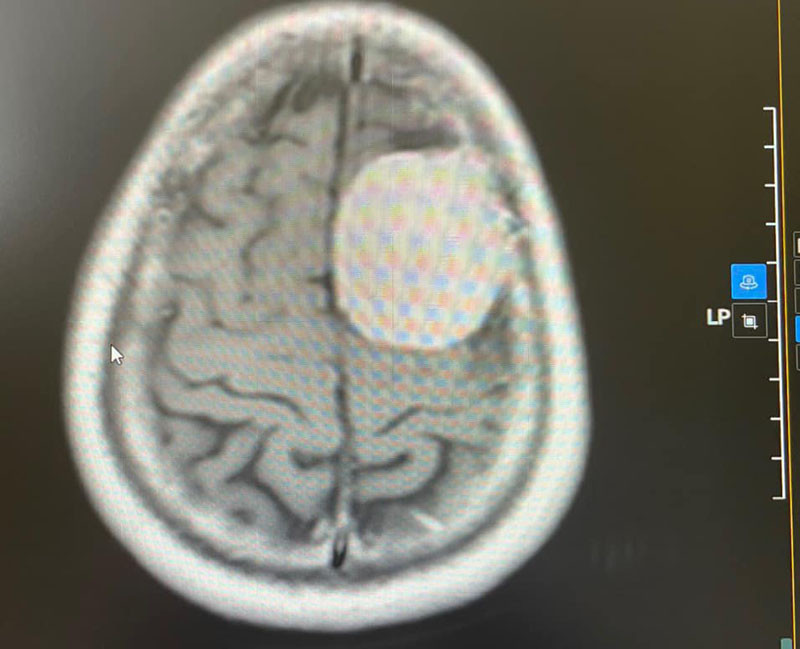

Các bác sĩ đã tiến hành khám và chỉ định chụp cộng hưởng từ có tiêm thuốc cản quang để tìm nguyên nhân và phát hiện khối u kích thước 36x48x54 mm vùng trán đỉnh trái của bệnh nhân. Sau ca phẫu thuật kéo dài hơn 4 giờ, khối u lớn trong não đã được lấy ra trọn vẹn.

BSCKII Mạc Hoàng Dương, Trưởng khoa Ngoại thần kinh, Bệnh viện Đa khoa tỉnh Bắc Giang, cho biết: “Khối u trong não của người bệnh rất lớn, phát triển vào sâu trong tổ chức não, lại nằm ở vùng sát với rất nhiều hệ thống mạch máu nên nguy cơ làm đứt và chảy máu trong khi phẫu thuật là rất cao”.